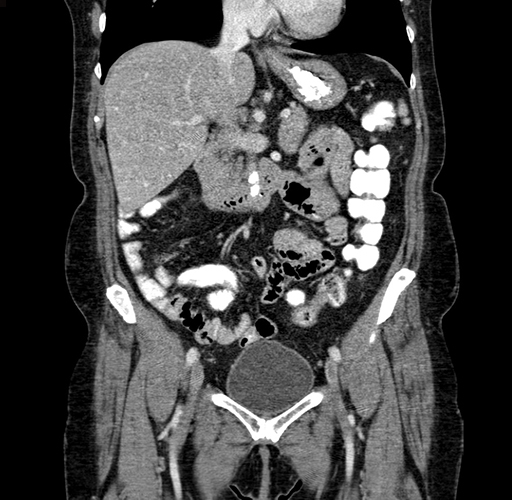

Pre-Chemo: Coronal Venous

Coronal Venous